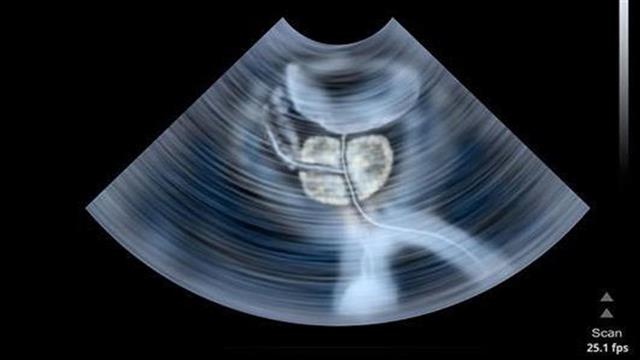

«Πρόκειται για  μια καινούργια μέθοδο απεικόνισης, η οποία συνδυάζει τη μαγνητική τομογραφία του προστάτη με το διορθικό υπερηχογράφημα. Πραγματοποιείται με τη λήψη μιας τρισδιάστατης εικόνας του προστάτη αλλά και της βλάβης (του όγκου) και  τοποθέτηση των εικόνων στον υπέρηχο που εκτελείται παράλληλα. Ένας αισθητήρας μας καθοδηγεί απευθείας στη βλάβη για τη λήψη βιοψίας, με απόλυτη ακρίβεια, μόνο από την ύποπτη εστία. Αυτό έχει ως αποτέλεσμα μικρότερο έως μηδενικό ποσοστό λοιμώξεων και τριπλάσιο ποσοστό ανίχνευσης  καρκίνων σε σχέση με τη συμβατική μέθοδο. Μόλις η βλάβη με ιστολογική αποδειχθεί ότι είναι καρκινική τότε με εξαιρετική  ακρίβεια καταστρέφεται, απευθείας με βελόνα (που φέρει την ίνα του laser) δια μέσω του δέρματος χωρίς τομή, αφήνοντας άθικτα τα υγιή κύτταρα και τους ιστούς του προστάτη», μας εξηγεί ο Δρ. Μερτζιώτης.